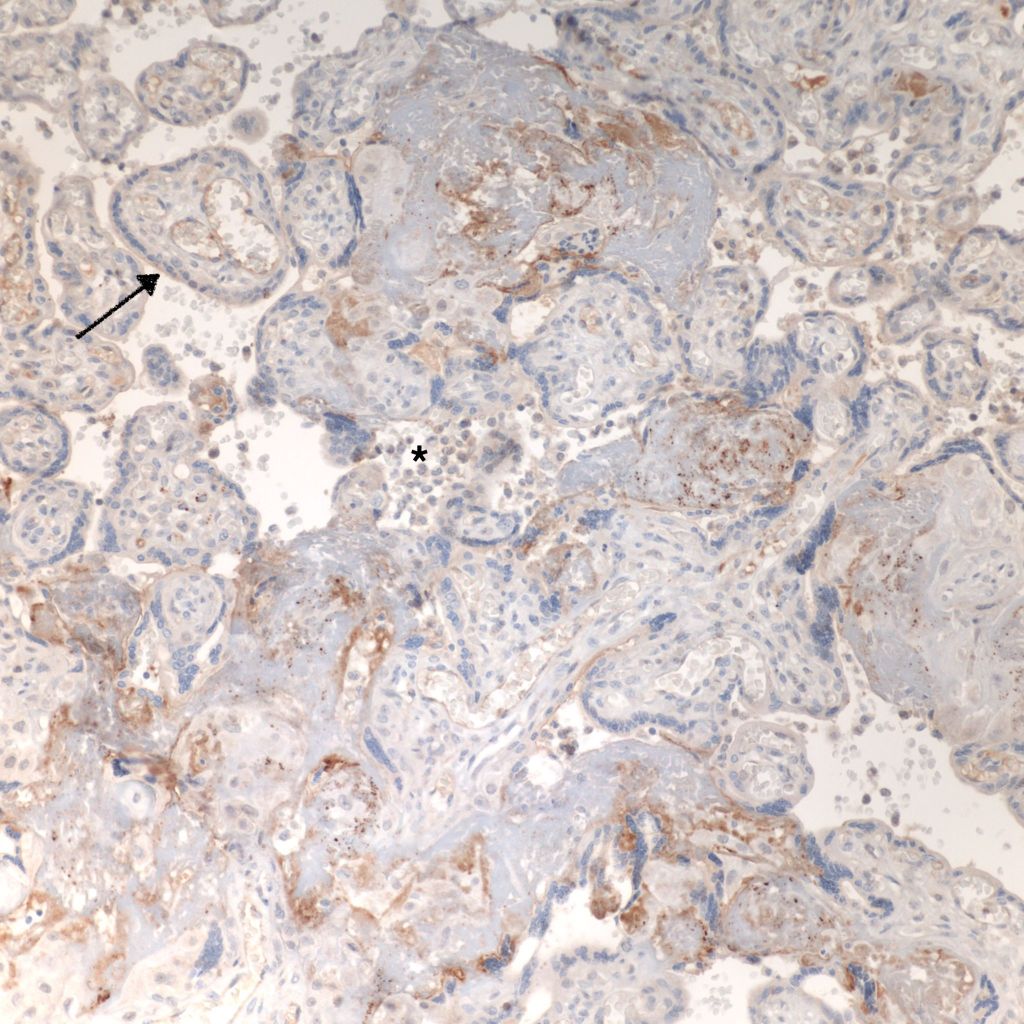

CD68 or alkaline phosphatase: to confirm that the intervillous cells are monocytes, but is not required for meeting the diagnostic criteria

C4d: to show evidence of complement fixation on the microvillous surface of the syncytiotrophoblast. While further study is needed, the subclassification of intervillous monocyte accumulations into those with and without complement fixation and the subclassification of villitis of unknown aetiology with intervillous monocytes into those with and without complement fixation may prove to be a useful distinction.

C4d: One study of CHIV compared 3 histologic groups of placentas demonstrating intervillous histiocytes: Few intervillous monocytes, massive intervillous monocytes, and intervillous monocytes associated with villitis of unknown aetiology18. Each group was further divided into subcategories based on the extent of c4d immunostaining of the microvillous surface of the syncytiotrophoblast. The outcome variables were fetal death or growth restriction. In the analysis, without a formal ROC study, it appeared that staining less than 25% of the villous surface was a natural cut off point from greater than 25%. As can be seen in the Table 1 of the raw data, that with rare exceptions, all the cases with less than 25% of c4d trophoblast staining, and often without any staining, were either associated with few intervillous monocytes, or with villitis. Fetal death or growth restriction was almost always associated with more than 25% of the villous surface stained with c4d. The lack of statistical significance in the comparisons is likely due to small sample size.

CHIV with prominent perivillous fibrinoid deposition

CHIV associated with Villitis of Uknown Etiology (VUE)

This pattern could be due to a primary cause of VUE with incidental chemotaxis of monocytes, two pathogenetically interrelated processes, or an incidental focus of VUE in a predominant CIIV disease. Currently, describing the extent of each process and its colocalization or lack of may prove useful until a better way to classify the co-existing lesions can be developed. One study has shown that there is a dichotomy between cases with c4d staining and those without c4d staining18.